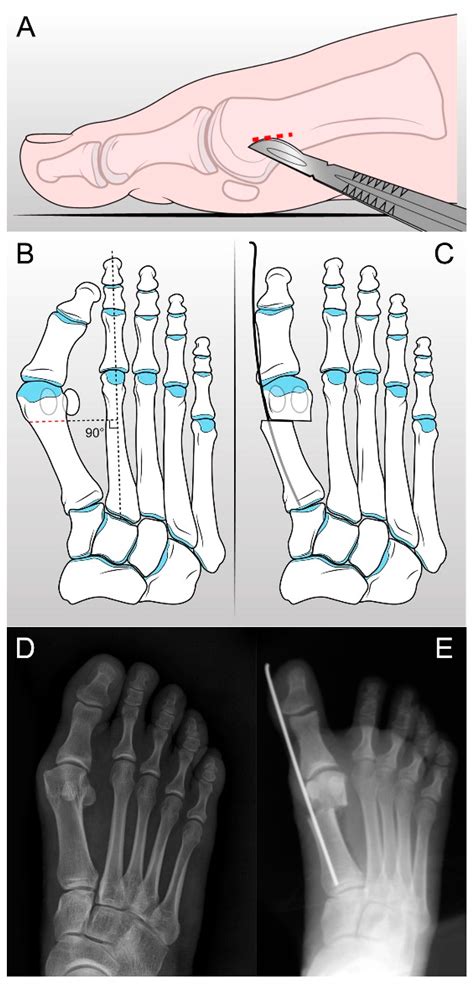

Hallux Valgus Correction, Hallux Valgus Splint, Hallux Valgus Toe ...